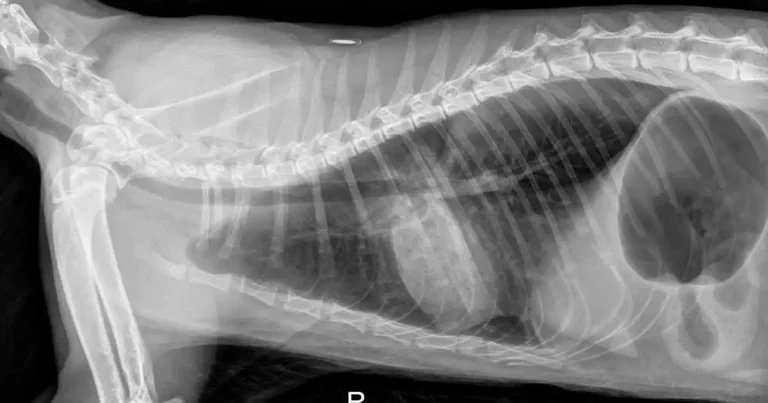

Figure 3. X-ray of a coughing cat showing changes consistent with bronchopulmonary disease.

- A young Maine coon presented with vomiting and dyspnoea and the x-rays were referred for interpretation (Figure 3). They show a diffuse bronchial lung pattern with consolidation of the right caudal lung lobe and overinflation of the lung. It is suggestive of bronchopulmonary disease (for example, chronic bronchitis/feline asthma) with air trapping and possibly mucoid plugging of the right caudal lung lobe).